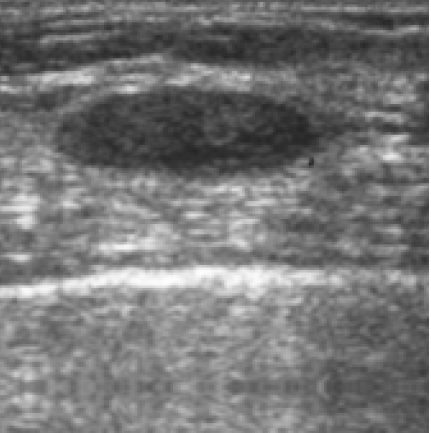

The target dataset was developed from 35 breast ultrasound scans that were segmented by an image-processing expert with extensive experience in breast lesion segmentation (the second author). The images, collected from the Web, are of different dimensions, ranging from to pixels (Figure 3, images resized for sake of illustration). These are the same images used to introduce EFIS originally [1].

Ultrasound images are generally difficult to segment, primarily due to the presence of speckle noise and low level of local contrast. It should be noted that the segmentation of ultrasound actually does require a complete processing chain, (including proper preprocessing and post-processing steps). However, the purpose of using these images was solely to demonstrate that the accuracy of the segmentation can be increased with the application of SC-EFIS.